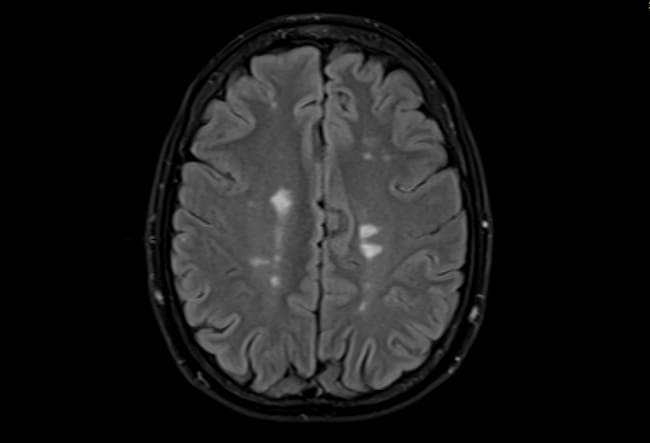

Científicos suecos creen que la "enfermedad del beso" engaña a nuestras defensas y puede causar esclerosis múltiple y afectaciones en el cerebro. / Paul Biris

Pero, ¿cómo? El estudio reveló que cuando nuestro sistema inmune intenta combatir el virus, unas células llamadas células T entran en acción. El problema es que, en su afán por protegernos, estas células se confunden y atacan a una proteína del cerebro llamada anoctamina.

A este fenómeno se le llama mimetismo molecular. Básicamente, nuestras defensas confunden las proteínas de nuestro cuerpo con las del virus. Es decir, cuando intentan eliminar la infección, terminan atacando a tu propio organismo por error, al no poder distinguir entre el invasor y tú.